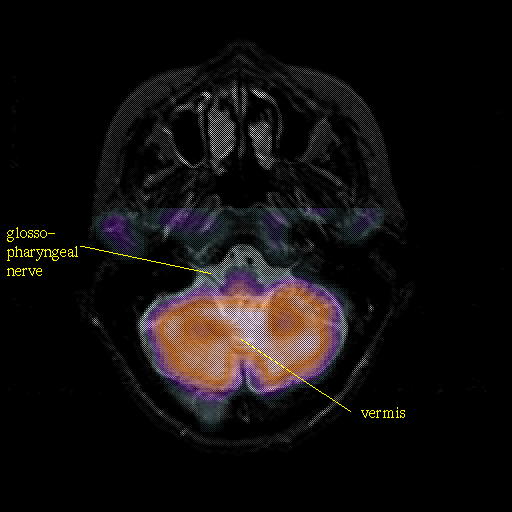

Pointers

Labeled